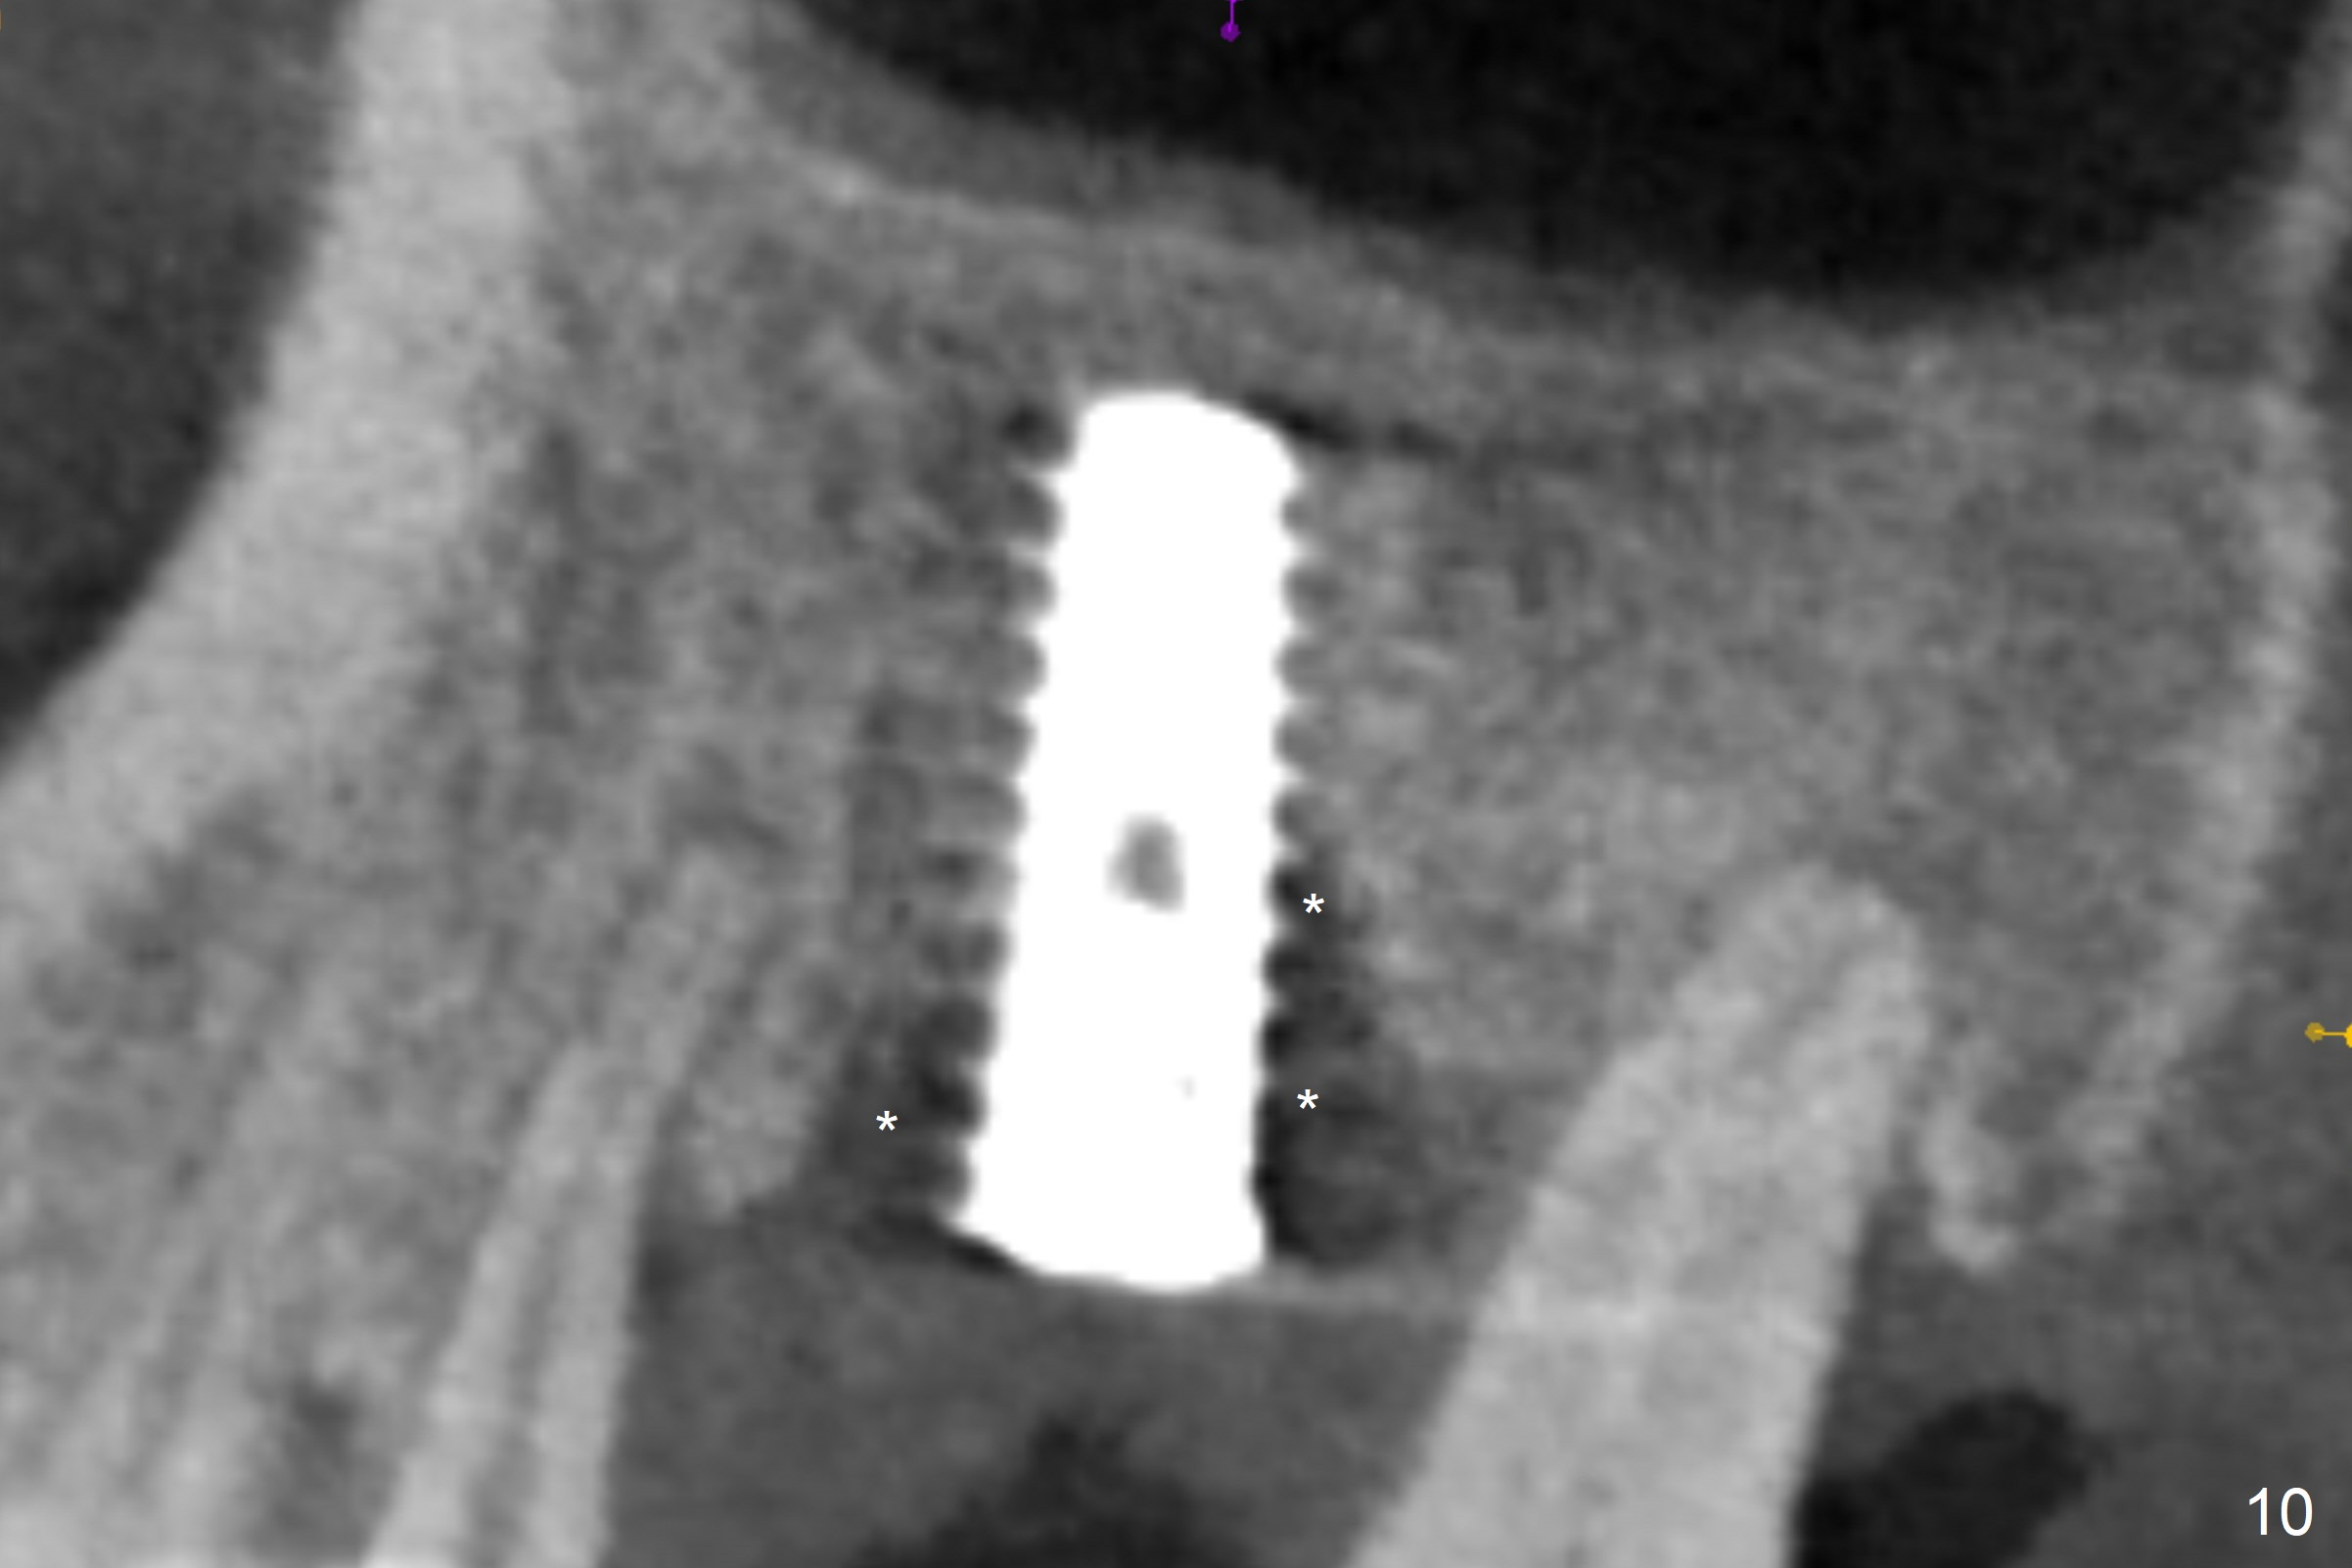

The amount of the bone graft mesial and distal the implant seems to reduce 3 and 4 months postop, respectively (Fig.6,7 arrowheads). When the acrylic is cut off 4 months postop, the bone graft is loose. The gingiva is unhealthy. The abutment and implant are loose. A healing abutment is placed (5x4 mm). The implant is torqued to 35 Ncm 6 months postop with the healing abutment reapplied. The patient will return for follow up nearly 9 months postop. A larger healing abutment will be used if the implant is stable. Two weeks later, use a smaller restorative abutment for easy impression. In fact the implant is unstable with #15 mesial shift due to abnormal occlusion with #17 (Fig.8). Bone density around the implant is low (* in Fig.9 (PA), 10,11 (CT sagittal, coronal sections)). A healing screw is placed for self healing. A 2nd option is to remove the implant (Fig.12), BEB (Fig.13) and place the implant deeper (Fig.14) or larger one (5.5-6.5x13 mm). The 3rd option is to place larger and longer implants (Fig.15 (tapered), 16 (cylindrical)). The implant access has partially closed 14 months postop, but there is a small buccal opening with sanguine exudate. Incision reveals severe bone loss around the implant; the mobile tooth #15 is extracted (Fig.17). After debridement and irrigation with normal saline, Vera Graft (Fig.18 *) and Collagen plug are placed with periodontal dressing.